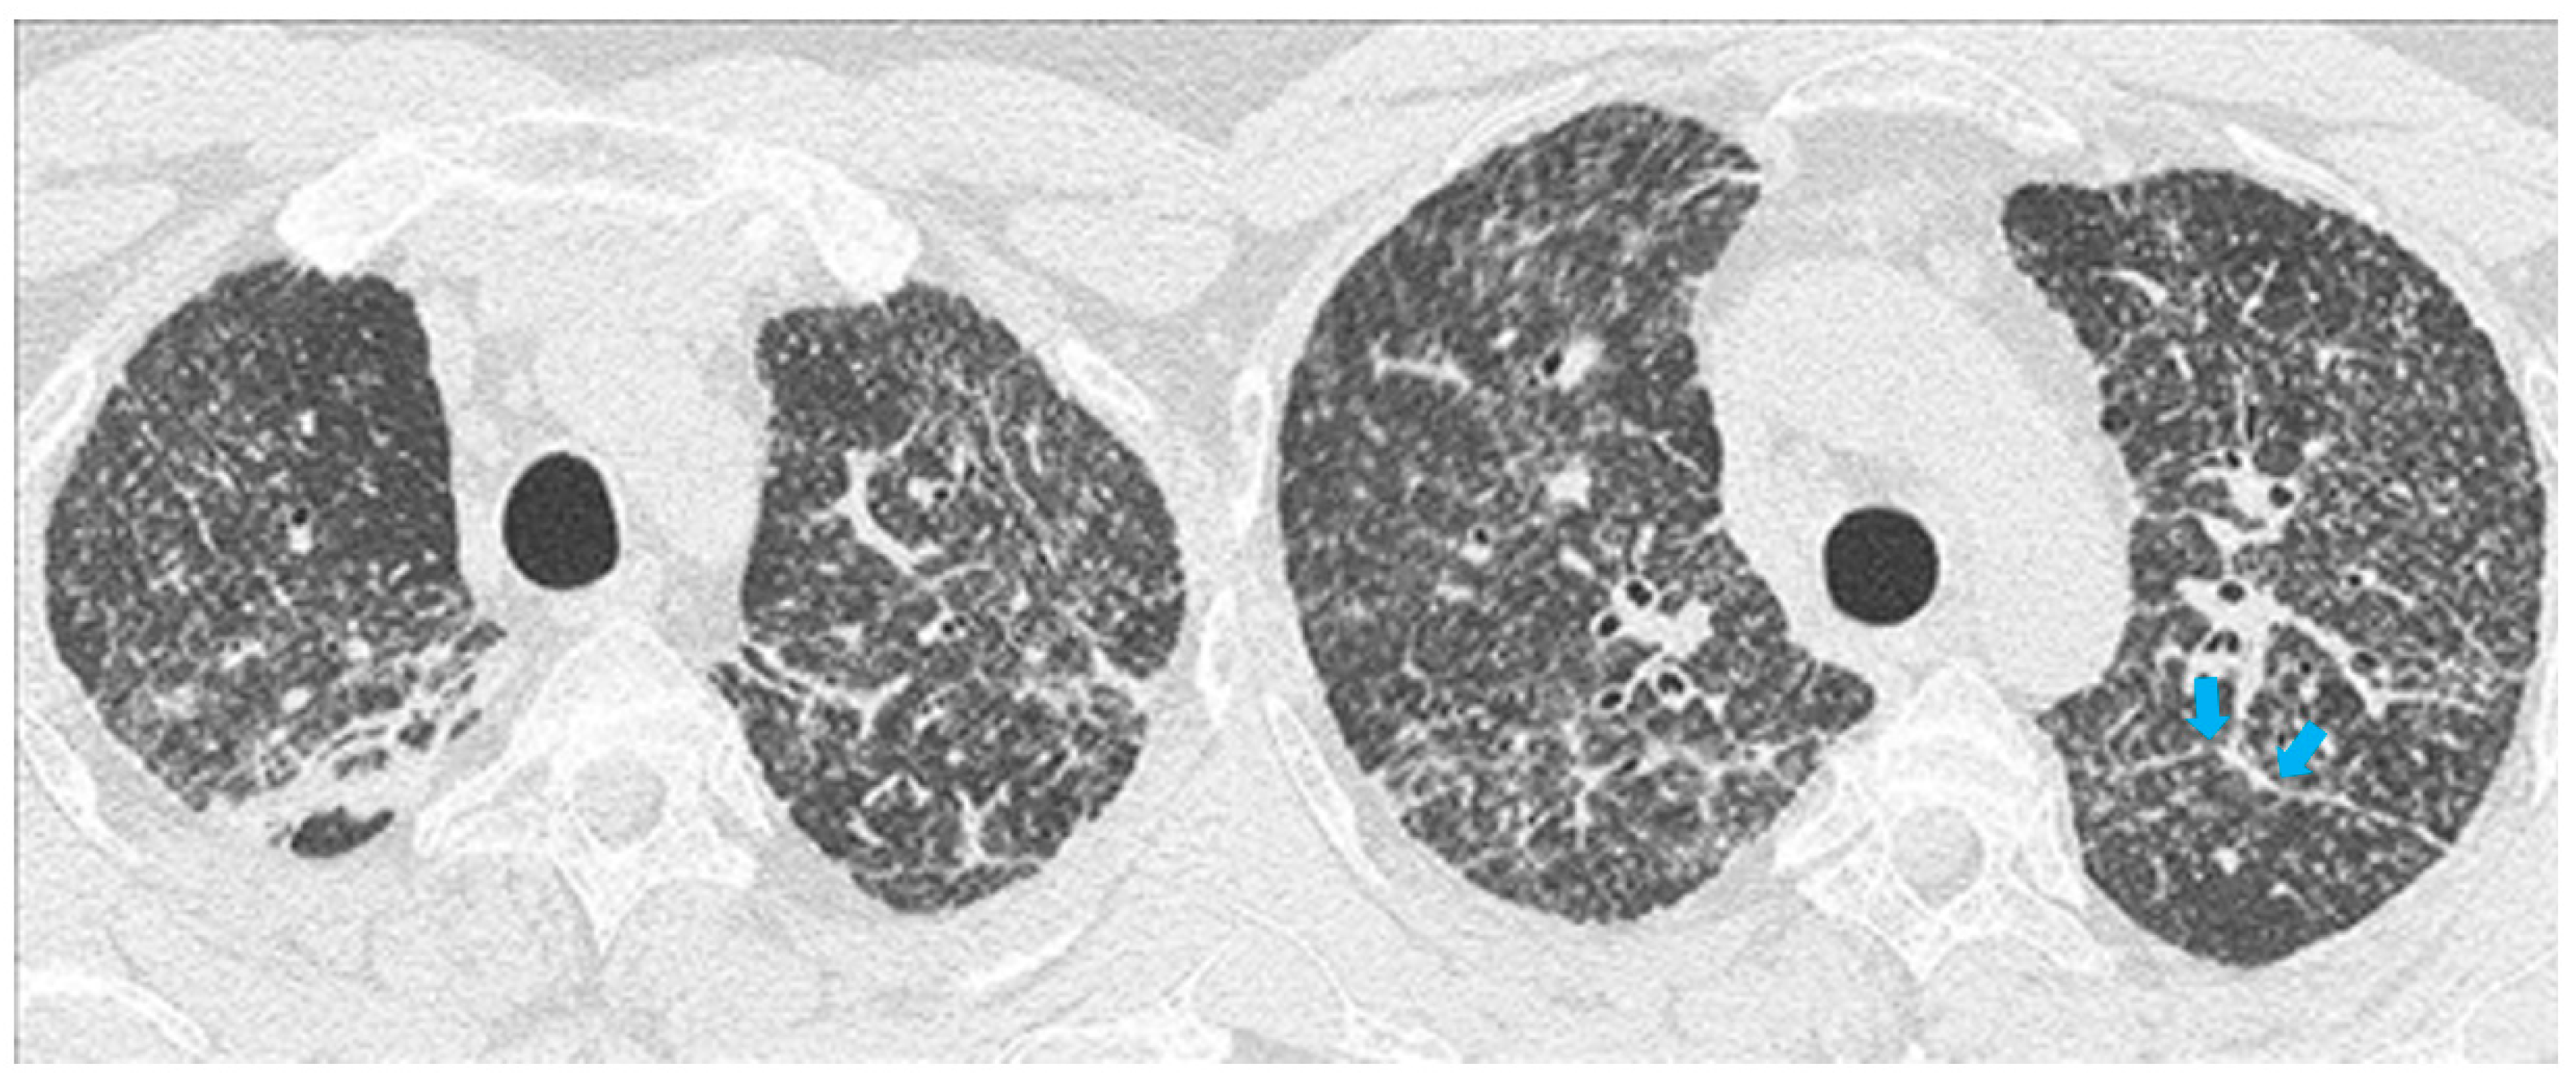

2.2. Typical and Atypical Manifestation of Pulmonary Sarcoidosis at HRCT

3.2. HRCT Findings of Lung Involvement from COVID-19

- Larici, A.R.; Cicchetti, G.; Marano, R.; Merlino, B.; Elia, L.; Calandriello, L.; Del Ciello, A.; Farchione, A.; Savino, G.; Infante, A.; et al. Multimodality imaging of COVID-19 pneumonia: From diagnosis to follow-up. A comprehensive review. Eur. J. Radiol. 2020, 131, 109217. [Google Scholar] [CrossRef]